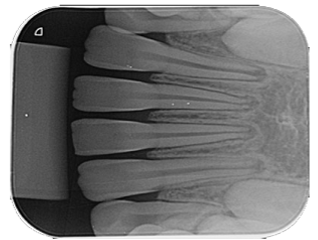

Para uma correta montagem das radiografias dentárias, o profissional deve possuir conhecimento do tipo de exame executado e dos elementos dentários presentes.

Diante disso, analise a radiografia a seguir:

Essa é uma radiografia do tipo: